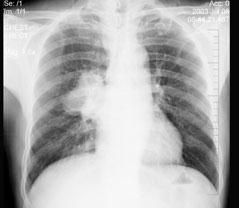

问题 男性,59岁,痰中带血就诊,X线检查如图,最可能的诊断是 ( )

选项 A、肺转移瘤 B、支气管扩张 C、右肺癌 D、右肺淋巴结肿大 E、结节病

答案 C